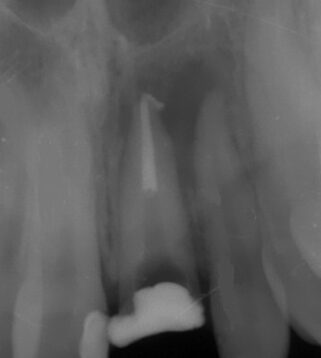

Chronic periodontitis of the 21st tooth (Photo 1 and 2).

The examination found a sinus tract with an active inflammatory symptomatology. The endodontic treatment failed to give any positive results. There was made a decision to extirpate the 21st tooth along with simultaneous placement of Alpha Dent Implant with its diameter of 5 mm, 13 mm long and closure of soft tissue defects with PRP membrane. The surgery was carried out without immobilization of mucosa-periosteal graft making it possible to attain a good aesthetic look of the gingival edge and harmonious “rose-and-white” ratio.